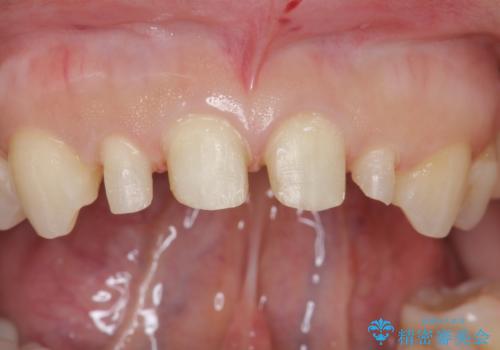

- 前歯が大きいのを揃えたいとのことでした。

少し削って長さを短くして様子を見ましたが、どうしても気になるとのことでした。

歯の向きは悪くなかったため、神経は取らずに治療しました。